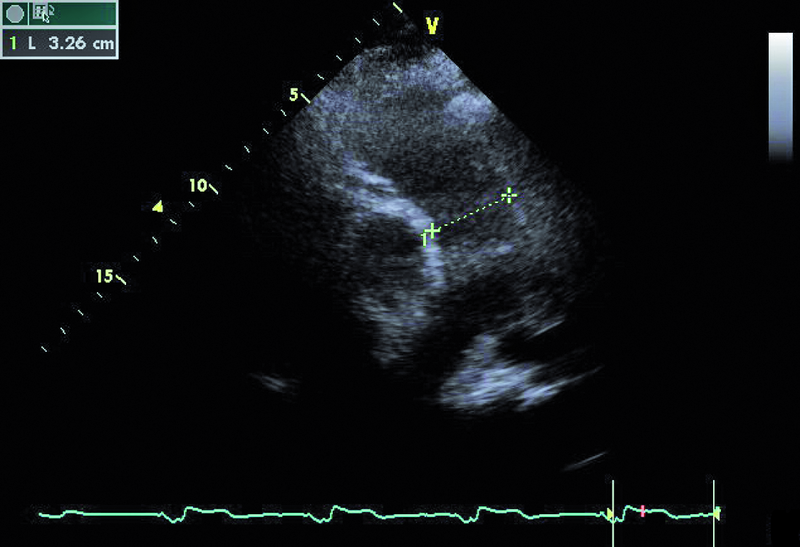

Mężczyzna, lat 59. Jakie patologie można rozpoznać na rycinach?

4. Poszerzony pień tętnicy płucnej (ryc. 3).